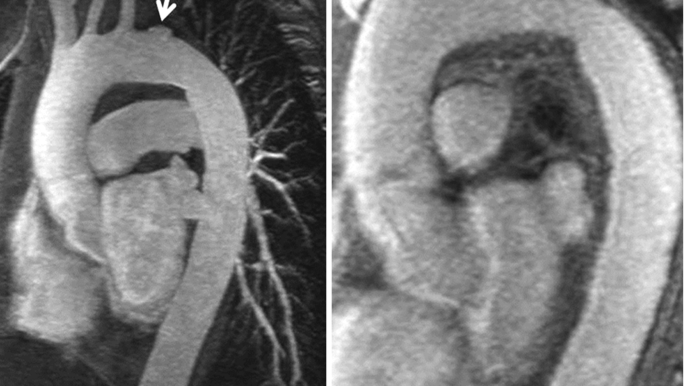

Developing biomarkers for heart disease diagnosis.

Pioneering novel biomarkers and diagnostic platforms for timely detection and monitoring of cardiovascular diseases in diverse settings.

We develop biomarkers and diagnostic platforms for effective cardiovascular disease management in various settings.

Discover novel biomarkers for diagnosing and monitoring cardiovascular diseases like heart failure and arrhythmias.